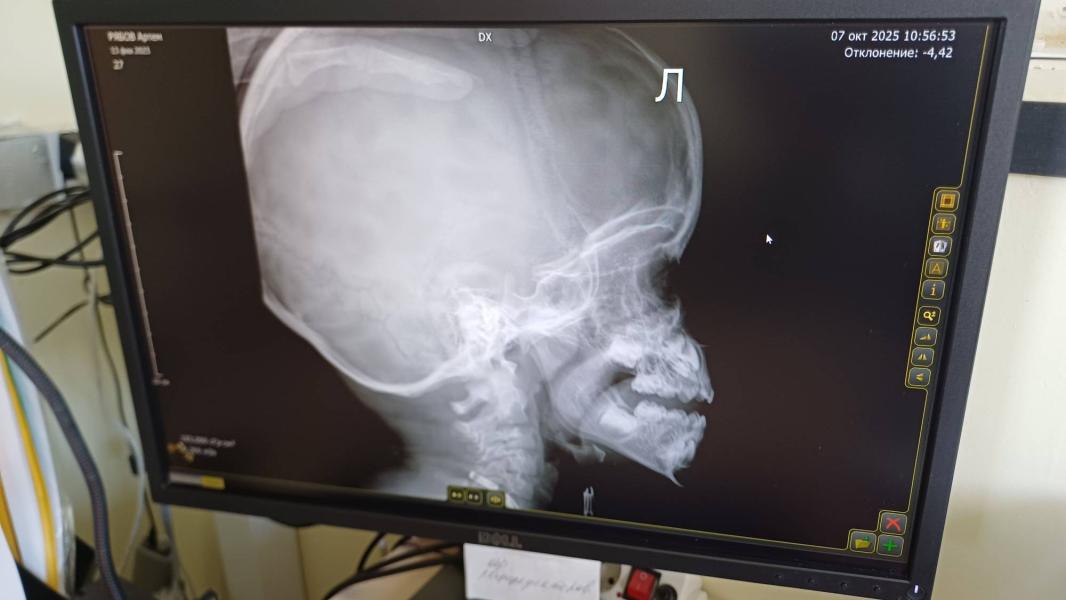

А отметила аденоиды и видно какая щель остается. Я бы сказала 2 степень

Но я не врач, это мое сугубо личное мнение, по информации с интернета !!!